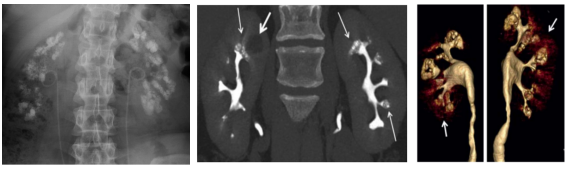

1.KUB(尿路平片):肾乳头和(或)锥体区可见簇状、扇形排列或放射状分布的多发高密度影。

图3 MSK结石的KUB,双侧肾区见多发密集的高密度影,结石呈簇状、放射状或粟粒状分布。

图4 MSK结石的增强CT排泄期相,可见囊状扩张的集合管被造影剂填充后出现“灯刷样"或"花束样"改变。

图5 MSK结石的增强CT三维重建,可见囊状扩张的集合管出现标志性的"花簇状"的景观